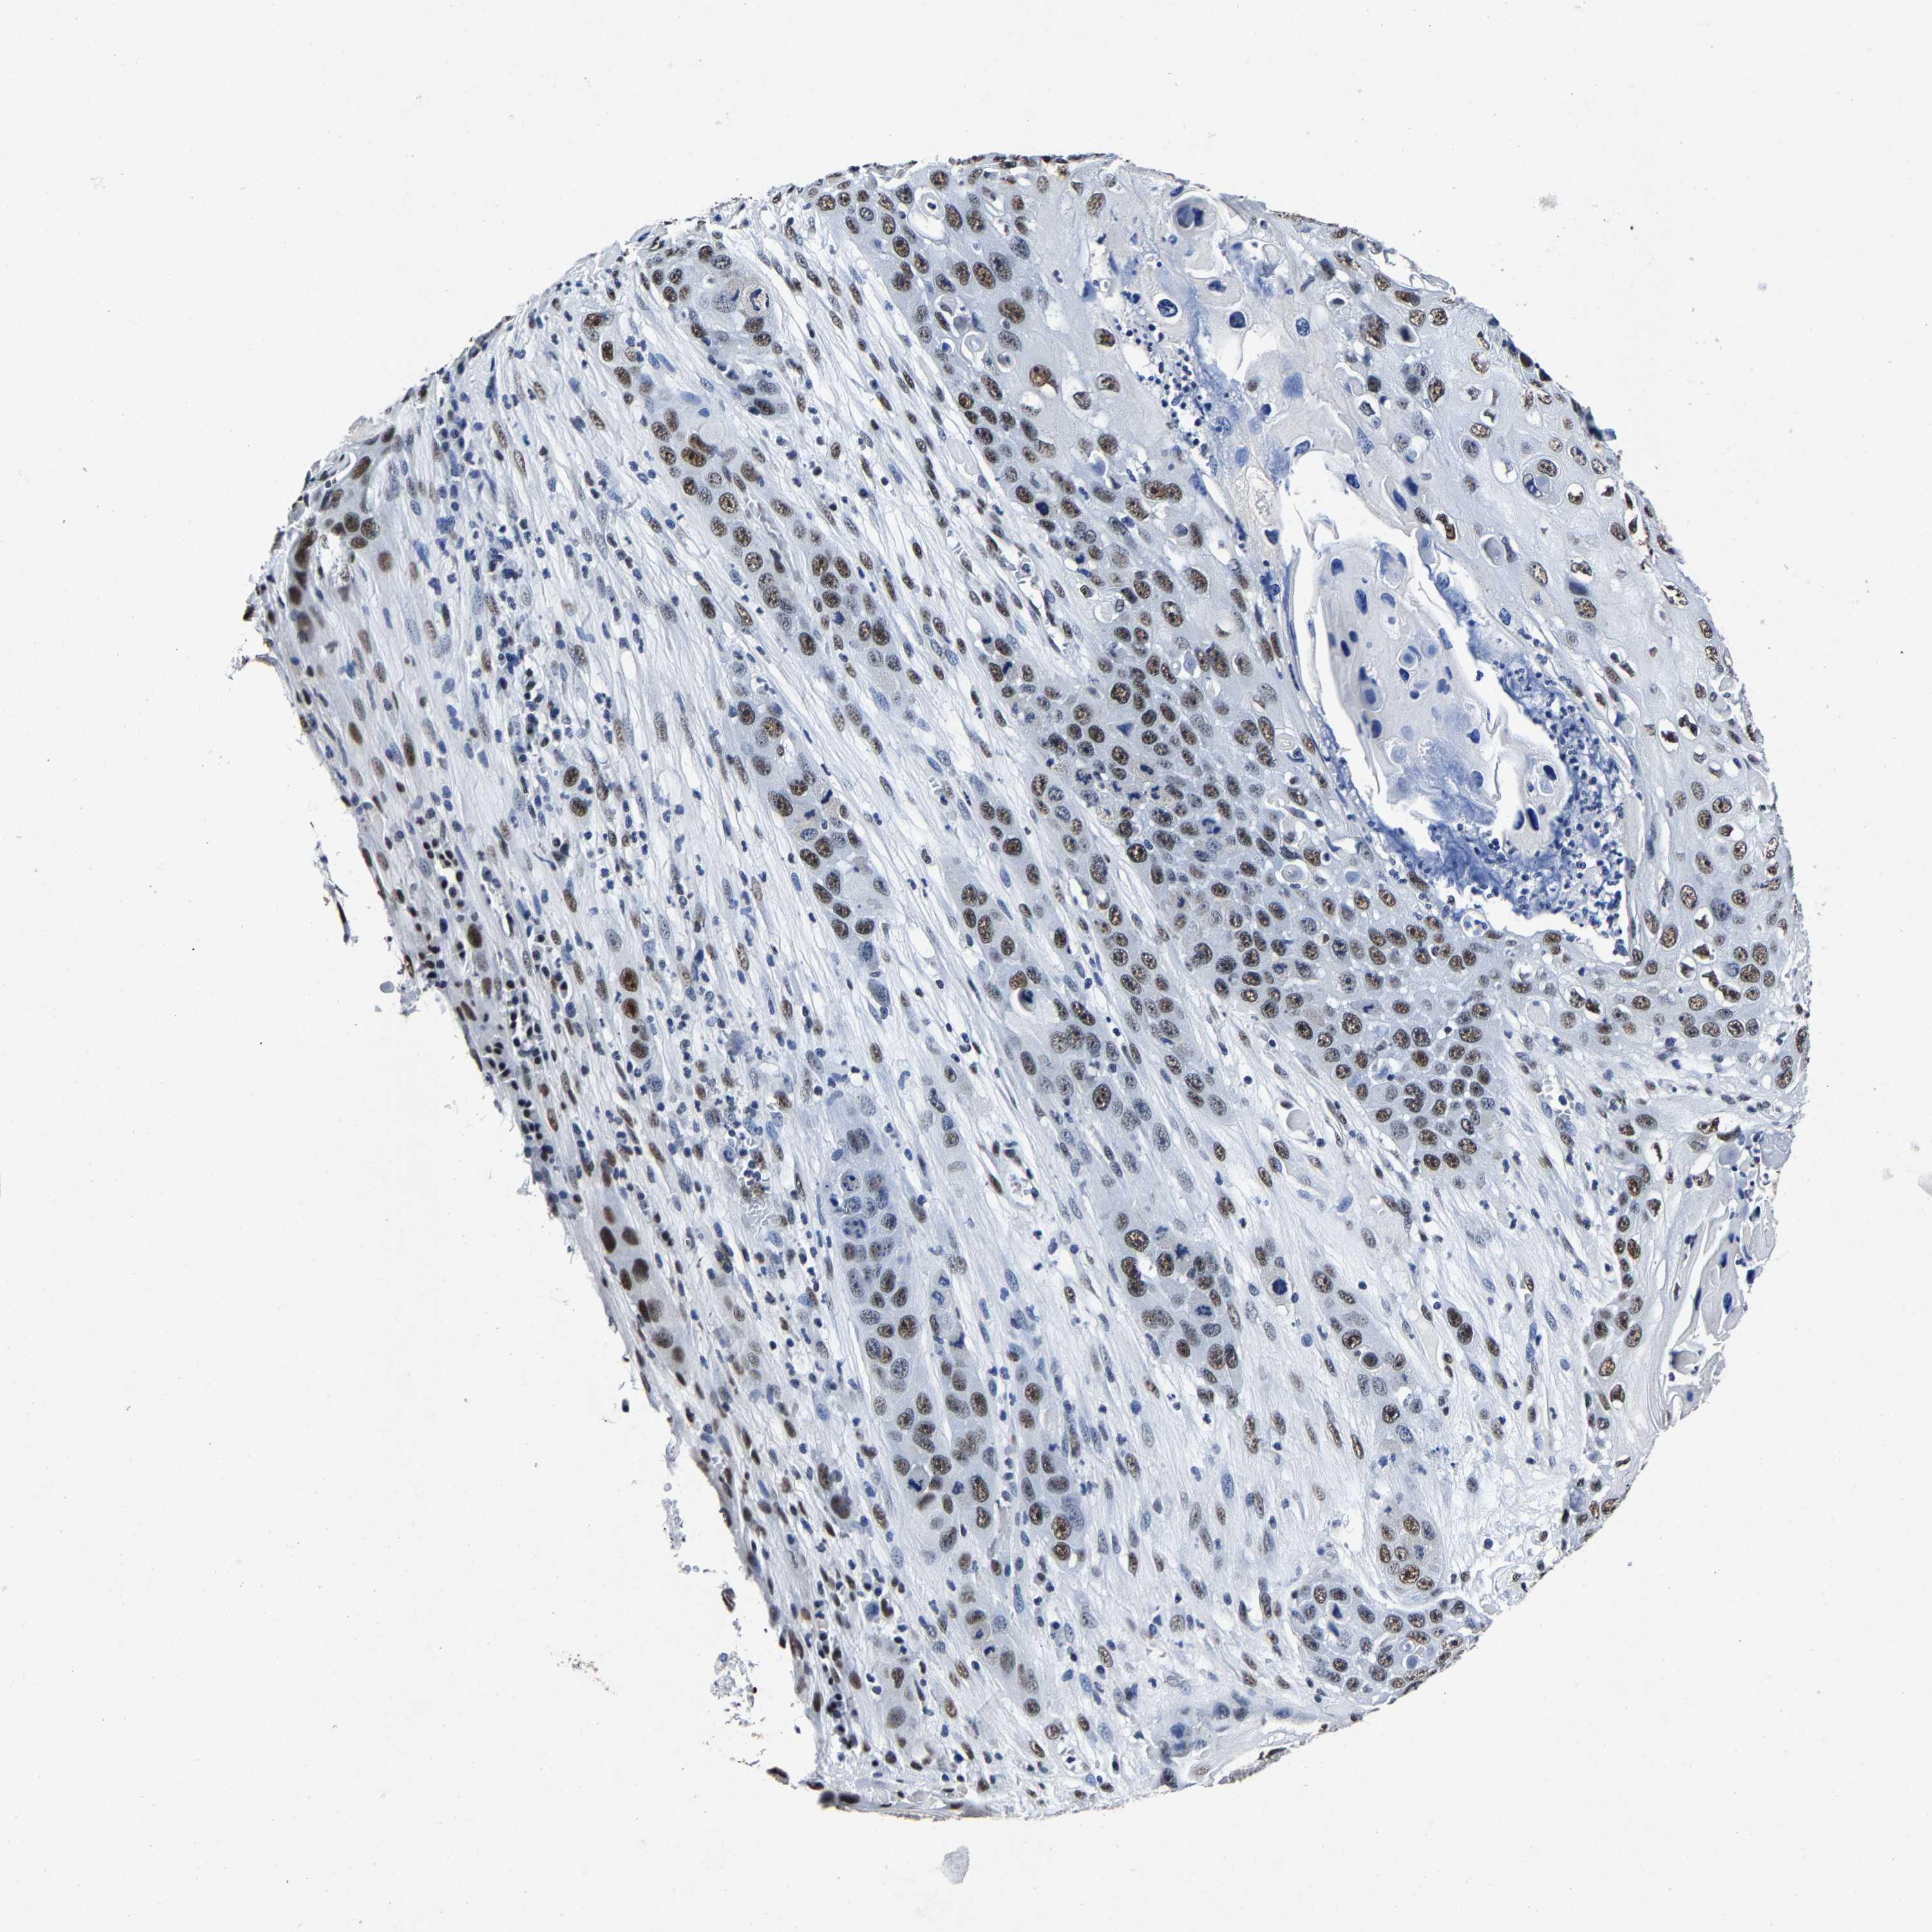

SKIN CANCER - Protein expressioni

A mouse-over function shows sample information and annotation data. Click on an image to view it in a full screen mode. Samples can be filtered based on level of antibody staining by selecting one or several of the following categories: high, medium, low and not detected. The assay and annotation is described here.

Antibody stainingi

Antibody staining in the annotated cell types in the current human tissue is reported as not detected, low, medium, or high, based on conventional immunohistochemistry profiling in selected tissues. This score is based on the combination of the staining intensity and fraction of stained cells.

Each image is clickable and will lead to virtual microscopy that enables deeper exploration of all samples and also displays staining intensity scores, fraction scores and subcellular localization as well as patient and tissue information for each sample.

Antibody HPA020448

Staining

High

Intensity

Strong

Quantity

>75%

Location

Nuclear

Basal cell carcinoma